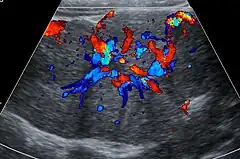

Unenhanced CT or MRI usually does not show the difference in intensity between the focal nodular hyperplasia and surrounding liver except when there is marked liver steatosis that reduces the attenuation of the liver, causing focal nodular hyperplasiato be hyperattenuating when compared with the surrounding liver. In the arterial phase CT or MRI, there is a strong enhancement not followed by washout. The lesion presents a slight hyperintensity or isodensity on portal venous phase or delayed phase images. There is also a presence of a central scar and absence of a capsule for the focal nodular hyperplasia.[7]